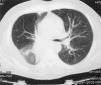

Varón de 64 años fumador con tos y expectoración hemoptoica de 2 meses de evolución